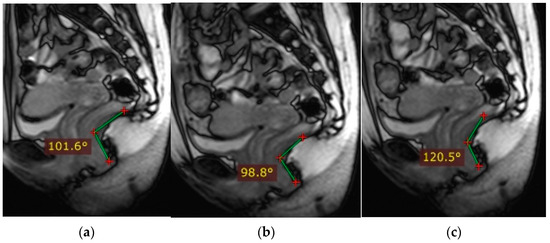

Figure 2 schematically shows the landmarks in images of the pelvic organs in normal conditions: The anorectal junction is the point of intersection of the anal canal axis with the axis of the lower ampullary segment of the rectum (measured from the back of the intestine). At rest, the anorectal junction is located above or at the level of the pubococcygeal line (PCL); when pushed, it shifts 3 cm below the (PCL). The anorectal angle varies depending on the tension or relaxation of the pubic rectus muscle. At rest, it is at 90–110°, and when the pubic rectus muscle is relaxed, it opens to 103–137°; when the pubic rectus muscle is strained, it becomes sharper.

Figure 2. Normal indicators of pelvic organ condition. (a)—anorectal angle at rest, (b)—anorectal angle during bowel obstruction and tension of the puborectalis muscle, (c)—anorectal angle during relaxation of the puborectalis muscle.